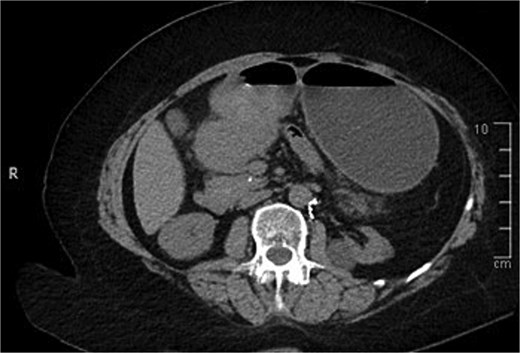

A computed tomography (CT) of the abdomen with IV portal venous contrast demonstrated proximal gastric dilatation due to a 7.6 cm gastric pyloric mass concerning for malignancy (Fig. 1). Other findings included small volume pancreatic parenchymal calcifications with no ductal dilatation. She was decompressed via nasogastric tube and planned for gastroscopy and feeding tube insertion. Gastroscopy demonstrated a partially obstructing extraluminal mass at the gastric antrum, able to be traversed to the second part of the duodenum (Fig. 2). A nasojejunal feeding tube was placed and the nasogastric tube was left in for decompression. An endoscopic ultrasound the following day demonstrated Doppler signal in the mass, confirmed to be a large 6.2 × 4.2 × 7.0 cm pseudoaneurysm arising from the GDA on a subsequent CT mesenteric angiogram (Fig. 3). Coil angioembolization of the pseudoaneurysm was successfully done via common femoral access (Fig. 4). She was commenced on NJ feeding and supplemental parenteral nutrition. She recovered well and was discharged on puree diet. Repeat imaging at 4 weeks demonstrated resolution of the pseudoaneurysm and returned to normal diet 6 weeks post presentation.

Contrast-enhanced CT of the abdomen. Axial view showing gastric outlet obstruction.